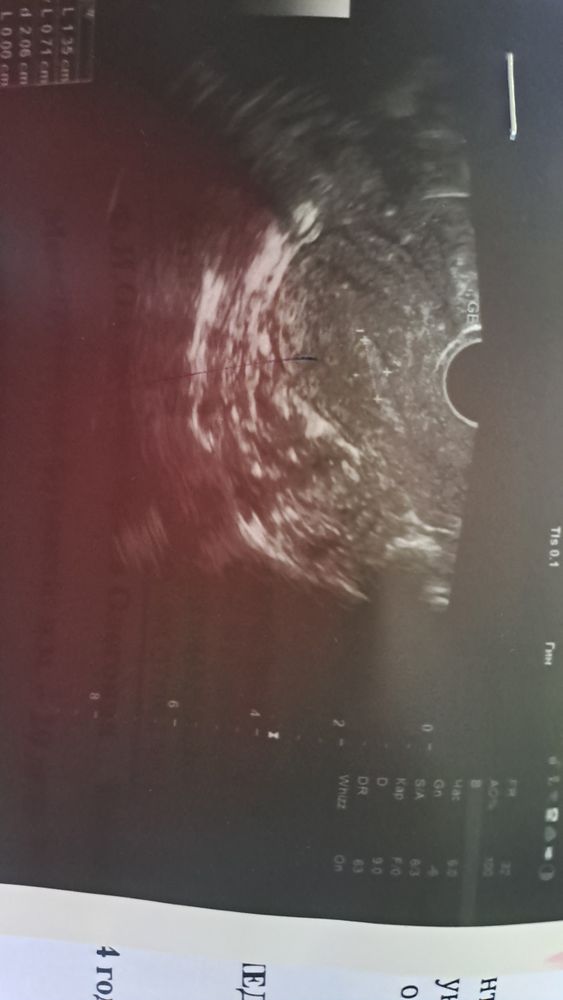

Девочки посмотрите узи 🙏 может кто знает сталкивался. Сходила на узи на 20 дц, предположили полип полости матки(На сколько всё плохо по узи, и могла ли врач ошибиться?

Белесый червяк - он самый. Сама такой же третий раз смотрю на своих УЗИ и третий раз пойду удалять.